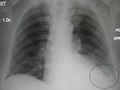

AP CXR showing right lower lobe pneumonia

Right upper lobe pneumonia as marked by the circle.